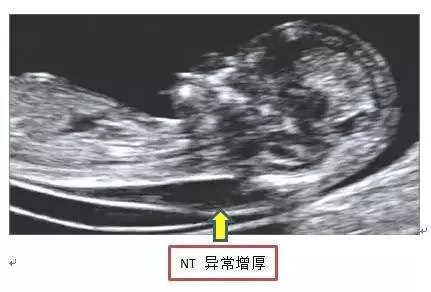

就是箭头所指这个地方的厚度啦!

NT增厚与染色体异常关系密切:常见有21三体、18三体、13三体;有研究显示NT 3mm时染色体异常风险增加3倍;NT 5mm时染色体异常风险增加25倍 。还可见于先天性心脏病 , 各种原因引起的胸腔压力增高 , 骨骼畸形 , 淋巴系统异常 , 羊水过多 , 宫内感染 , 贫血等 。

NT常用的判断标准:一般NT大于等于2.5mm视为异常 。厚度增加 , 只是发生胎儿异常的可能性增加 。NT增厚越明显 , 胎儿异常机会就越高 , 异常程度也越严重 。NT值正常 , 亦不能说明没有问题 。值得一提的是 , 约80%-90%的NT异常胎儿是一过性病变 , 即如果胎儿没有任何染色体或心脏等问题 , 即便NT增厚也不代表任何问题 。

当孕早期NT异常怎么办呢?应进行进一步检查 , 如进行相关染色体检查等 , 对染色体核型正常者 , 还需要密切追踪观察 , 排除有无先天性心脏发育异常及其他结构异常 。